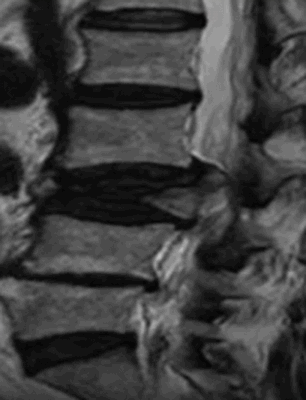

Осложненный компрессионно-оскольчатый перелом тела позвонка в грудном отделе на МРТ

На срезах можно увидеть хрящи, связки, мышцы. Применение специальных последовательностей позволяет изучить сосуды, нервные волокна, головной и спинной мозг, лимфатические структуры. Существенным недостатком метода является его низкая информативность относительно состояния костной ткани. МР-сканирование плохо отображает участки с малым содержание влаги.

Покажет ли МРТ перелом, зависит от структуры поврежденной кости. Врач может заподозрить деструкцию по характерным признакам. Например, о скрытом переломе будет говорить отек костного мозга. При этом результаты рентгена могут не показать повреждение.